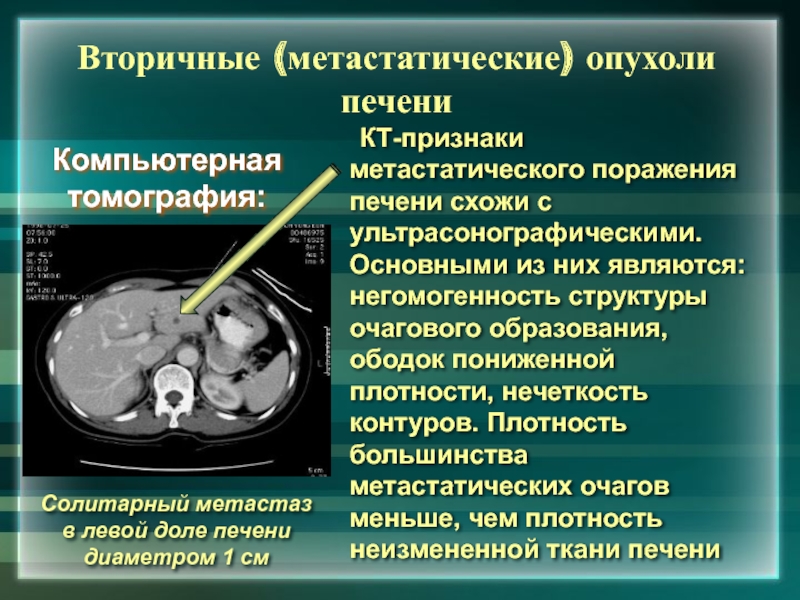

Метастатические поражения печени в ультразвуковом изображении характеризуются